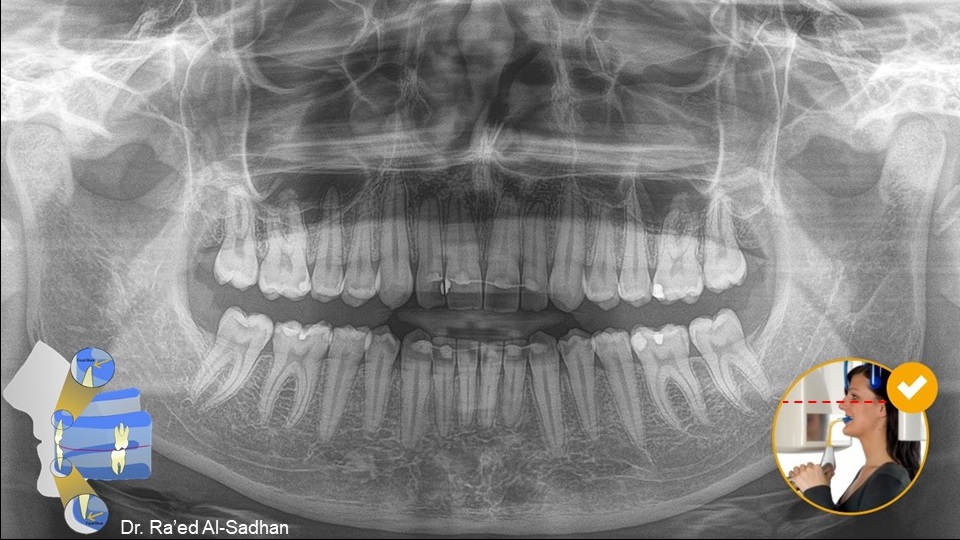

الوضع الصحيح للرأس أثناء التصوير البانورامي يضبط فيه طرف الخط الضوئي الأفقي مع محور فرانكفورت Frankfort plain على أعلى فتحة الأذن (upper margin of ear canal (porion ثم رفع أو إنزال ذقن المريض حتى يلامس الطرف الآخر لخط الضوء أسفل محجر العين inferior margin of orbit (orbitale)

وعندما يوضع الرأس في هذا المستوى وتعض أطراف الثنايا على الثلمة التي في العود الذي في جهاز الأشعة incisal pin تكون الأسنان في وسط طبقة التصوير لجهاز الأشعة البانورامية وتظهر صورتها واضحة دون تشوه.